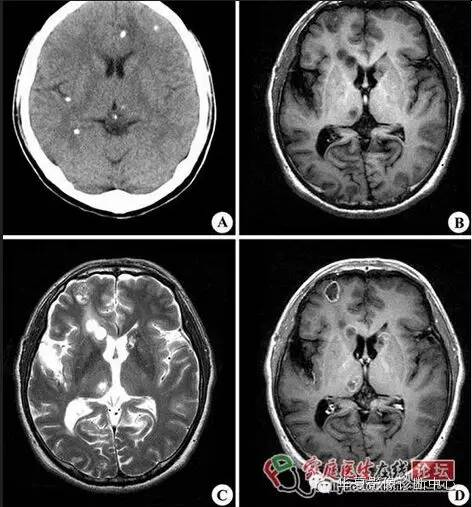

30.白靶黑靶征:

脑猪囊尾蚴病在CT平扫大多表现为小园形囊性病灶,大小为4~6mm,CT上为类圆形低密度内可见点状高密度,即所谓黑靶征。或在MRI上呈长T1长T2信号,部分病灶在T1WI上黑色的低信号内见到点状高信号,即黑靶征;在T2WI白色高信号内见到点状低信号,即白靶征。

脑囊尾蚴病,脑实质囊虫CT显示多发的圆形或卵圆形大小不一(0.1~0.5 cm)的结节状高密度影及(或)多个类圆形低度密度灶,边缘可见小点状高密度影,直径0.5~1.5 cm,部分病例病灶显示不清楚,仅见大片低密度区,类似脑炎改变。少数病例可见大囊型病灶,直径达7~8 cm,多为单发或仅有几个病灶。脑室内囊虫为圆形囊状,直径为1~4 cm,边缘光滑,稍低于脑脊液密度,或近似脑脊液密度。脑池、颅底部蛛网膜下腔囊虫呈葡萄状低密度病灶,囊壁有浅淡强化。可有脑积水表现。

脑囊尾蚴MR表现:脑实质囊虫:1)多发小囊型,系多个存活期囊尾蚴并存的表现。MR表现为双侧大脑皮质区有多个散在分布的小圆形或卵圆形小囊,直径0.3~0.8 cm,呈长T1WI、长T2WI信号,壁内可见偏心型小点状影,即囊虫头节,呈短T1WI、稍短T2WI信号改变,周围水肿不明显。Gd-DTPA增强扫描,囊壁呈环状强化,头节呈点状强化。2)大囊型,系一个巨大囊尾蚴或多个囊尾蚴融合而成的表现。MR表现为脑实质内巨大的圆形或卵圆形囊腔,其内无头节,信号与脑脊液一致,呈长T1WI、长T2WI信号,周围可合并脑水肿,有占位效应。Gd-DTPA增强扫描,大囊本身多无强化,若周围有纤维组织增生,可呈环状强化。脑室内囊虫亦引起脑积水,MRI表现为囊虫所在部位脑室呈不对称性增大,呈长T1WI、长T2WI信号,存活期囊虫多较脑实质型虫体体积大,直径可>2 cm,囊壁上可见偏心型头节影呈稍短T1WI、短T2WI信号。Gd-DTPA增强扫描,囊虫存活期囊壁无强化;退变死亡期囊壁可明显强化。脑池、颅底部蛛网膜下腔囊虫MRI表现为葡萄串样异常信号影,呈长T1WI、长T2WI信号,纤维间隔呈等T1WI、短T2WI信号,无囊虫头节。Gd-DTPA增强扫描,囊壁及间隔可轻度强化。 医学百科网 | YxBaike.Com